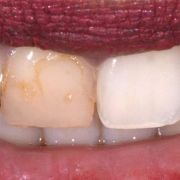

I used one hue (B), three opacities (Enam.,Body, Dent.) and two different chroma of the same hue (B1,B2).

Different posing revealing different natural light reflections on the tooth!